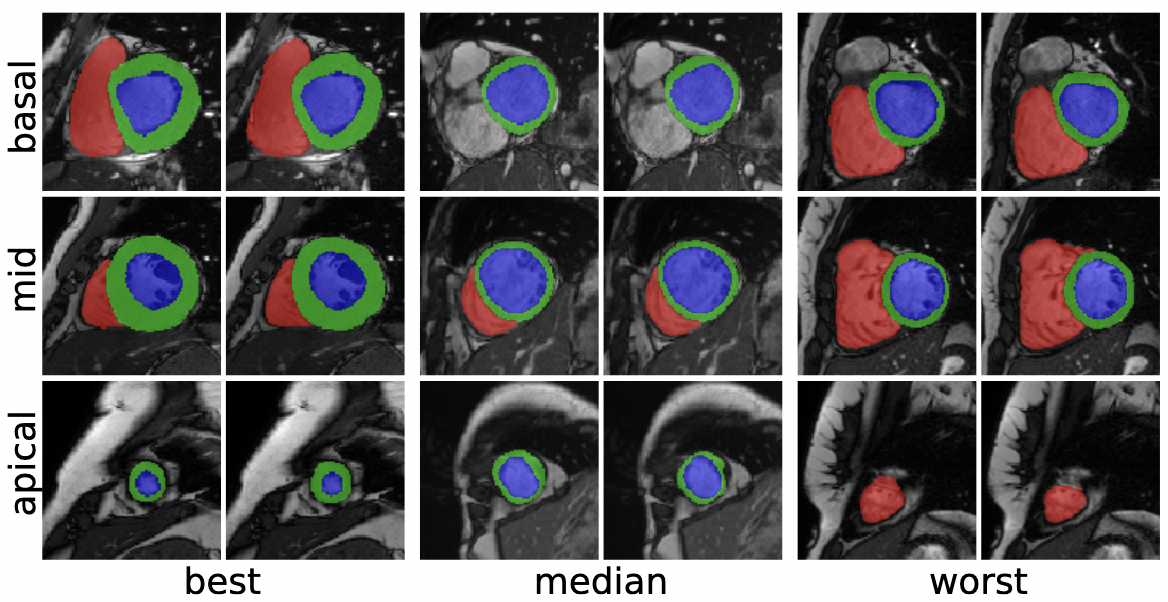

An exploration of 2D and 3D deep learning techniques for cardiac MR image segmentation

Christian F. Baumgartner, Lisa M. Koch, Marc Pollefeys, Ender Konukoglu

International Workshop on Statistical Atlases and Computational Models of the Heart, 111--119 (2017)

preprint URL